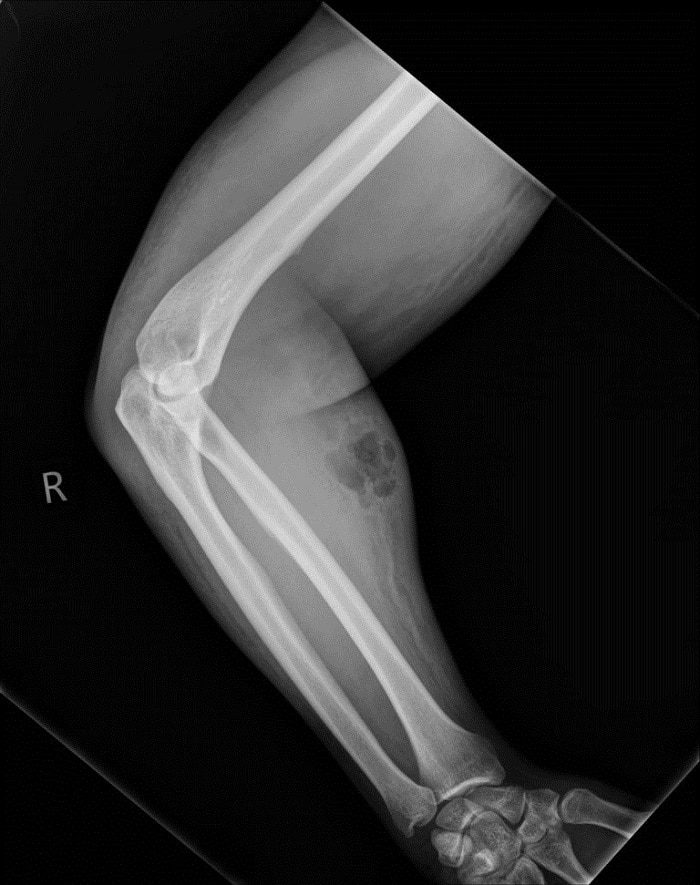

Tellement surpris par ce cas atypique, il est même publié dans l’Irish Médical Journal. Quant aux effets, ils ne sont pas si mirobolants que cela. Après avoir passé son avant-bras aux rayons X, les médecins se sont rendu compte que de l’air était coincé sous la peau à cause du sperme. Ils lui ont donc prescrit une thérapie anti-microbienne par intraveineuse et rapidement, le patient était sur pied et sans mal de dos !